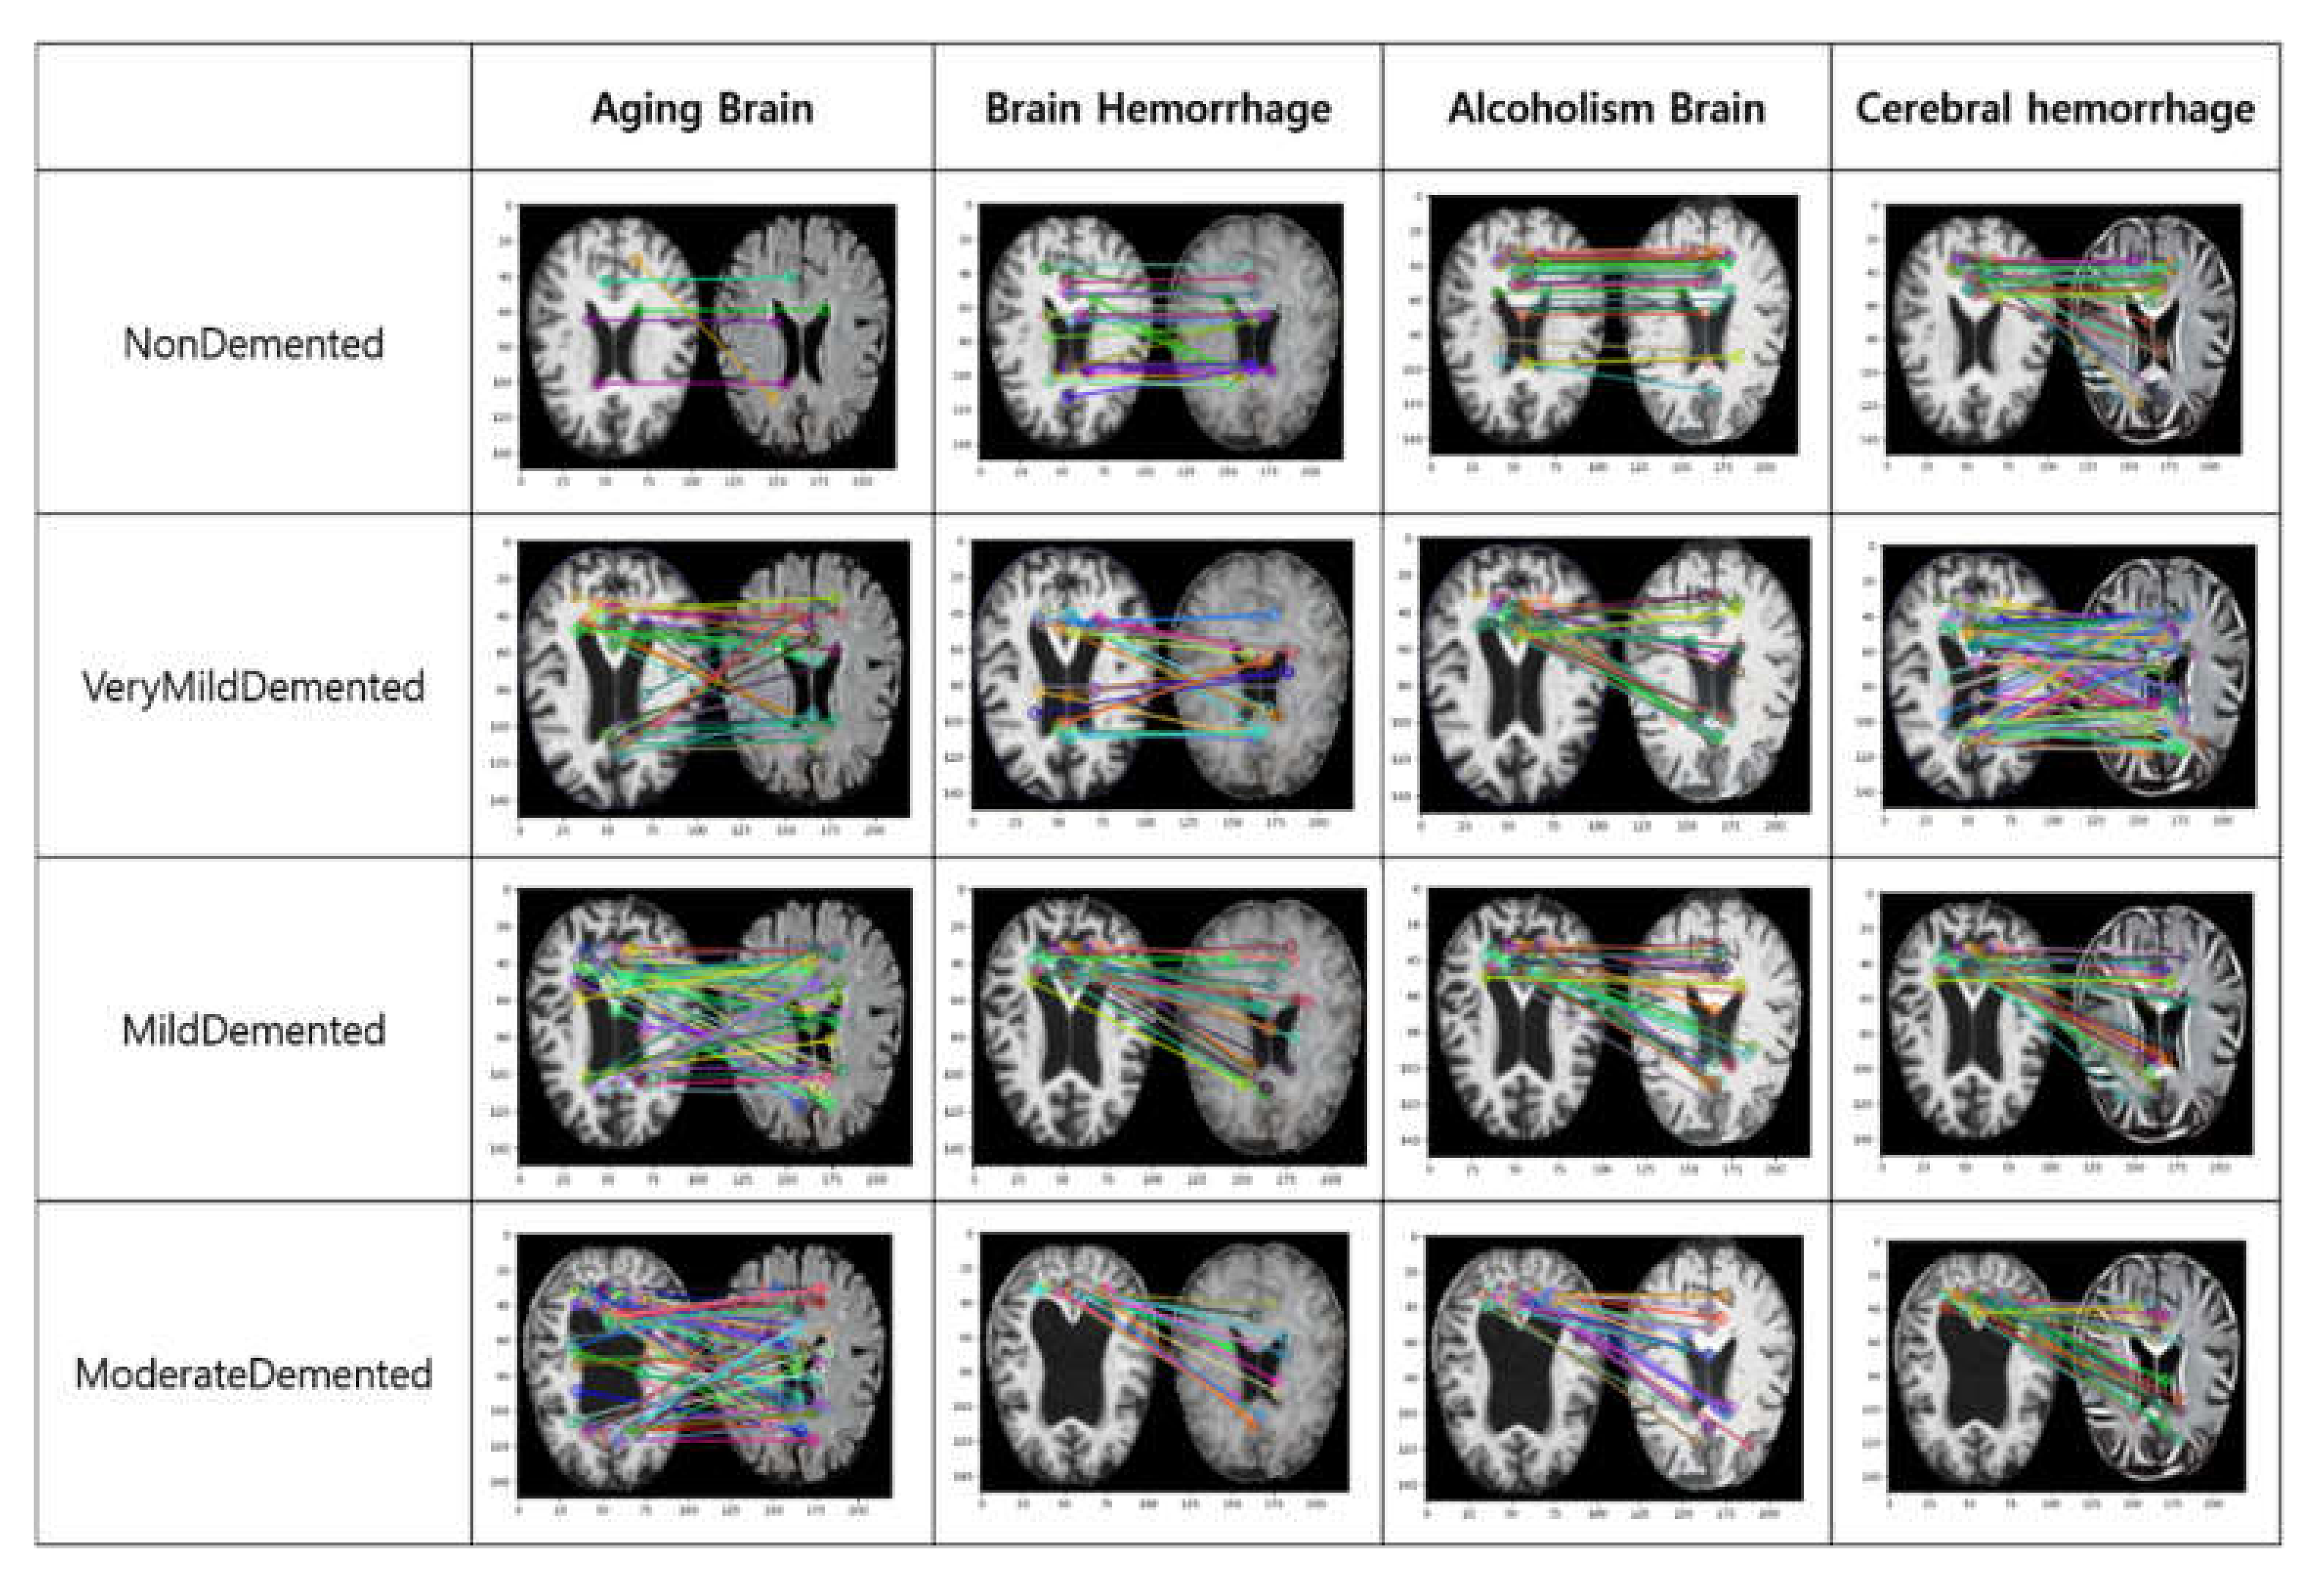

- Image style transfer is a method for transforming image style by keeping the main form of the image using two-image data in the computer vision and, additionally, applying the desired style. Through this, changes in the brain are predicted by transferring the factors affecting dementia.

- This is a method for collecting features and evidence needed for management, prevention, and diagnosis through an analysis of various factors that affect Alzheimer’s disease and monitoring the dementia condition according to changes in the brain. The factors affecting dementia are extracted through regression analysis, and the regression coefficient is used as the degree of impact. In addition, images of the factors affecting it are extracted, and results from the regression analysis are collected.